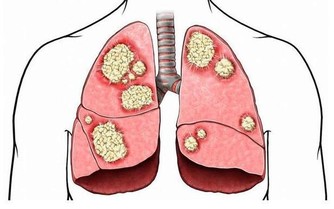

說到癌症,每個人都害怕,可是很多癌症其實都是我們自找的!

目前的科普信息並不難獲得,但近年來我國的癌症發病率還在不斷上升,

有一個重要原因就是很多人對於防癌知識只是口頭說說,沒有真的做起來!